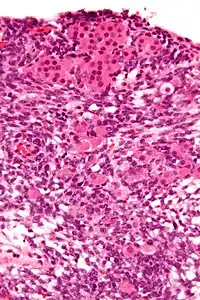

| Micrograph of a Sertoli–Leydig cell tumour. The Leydig cells have abundant eosinophilic or light pink cytoplasm. The Sertoli cells have a pale/clear cytoplasm. H&E stain. | |

The tumour is subdivided into many different subtypes. The most typical is composed of tubules lined by Sertoli cells and interstitial clusters of Leydig cells.